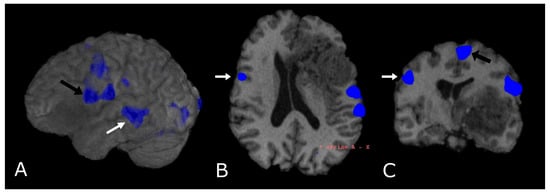

4.2. Diffusion Tensor Imaging: Technical Notes and Clinical Application

4.2.1. Tumor Grading and Extension

4.2.2. Presurgical/Intraoperative Assessment

4.2.3. Radiotherapy/Radiosurgery Planning

4.2.4. Differentiation between Recurrent Tumor and Radiation Injury